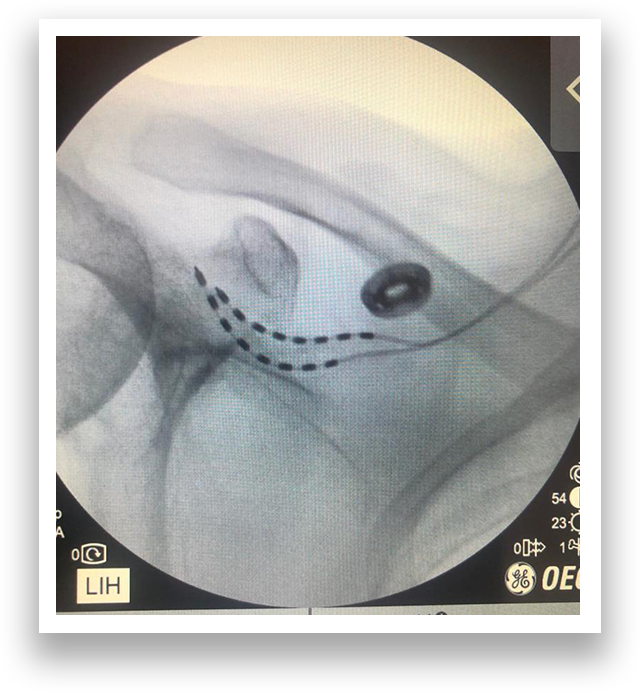

X-ray/MRI scan overlay